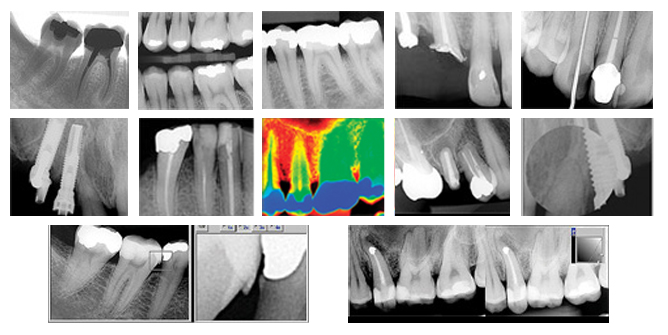

4. Digital X-Rays (intra-oral)

We all have come to recognize that we must reduce our exposure to any form of unwanted radiation. Our practice therefore moved from film based intra-oral x-rays to digital x-rays several years ago. To have an x-ray of your teeth made, a computer sensor is placed in your mouth and it requires only 1/10th of the radiation necessary for film x-rays.

Film based x-rays take several minutes to be chemically developed while digital x-rays are instantly viewed on screen ( above you ) and on the dentist’s screen. You instantly see a massive image which is then explained in clear terms. For our planet, there are no toxic x-ray chemicals poured down the drain at the end of the day. Let us keep it GREEN. Digital x-ray images are stored, compared with historical ones and reviewed at the click of a button, and most of all, they can be emailed to anyone if required, for a second opinion. Modern practices can incorporate digital x-rays into a patient’s records, unlike films.